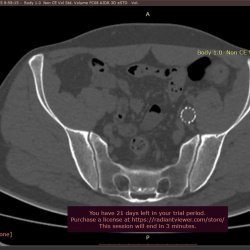

25.02.2025 - 13:07

М. 72 лет, с 2021 года каждые 2-3 месяца вскрывается свищ в левой подвздошной области. Эндопротез и позвоночник интактны. Какую этиологию хронического абсцесса можно предполагать по...